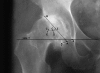

Methods: We compared hip offset of arthritic and contralateral normal hips on radiographs in 82 patients (82 hips) who had THA. We used computer navigation in all patients with the aim of reconstructing the hip offset and to compare hip offset change to the quantitative change of the hip COR.

Results: The preoperative radiographic change to equalize the offset ranged from -12 to +21 mm (mean, 1.5); postoperatively the change was 1.4 ± 6.4 mm and was within ± 6 mm in 78 of 82 hips. As COR displaced superiorly from 3 to 6+ mm the offset had to be substantially increased. Only with COR 0-3 mm superior and 0-5 mm medial was offset always within 5 mm.

Conclusions: Hip offset reconstruction was directly related to the position of the hip COR, and navigation allowed quantitative control of offset and hip length.